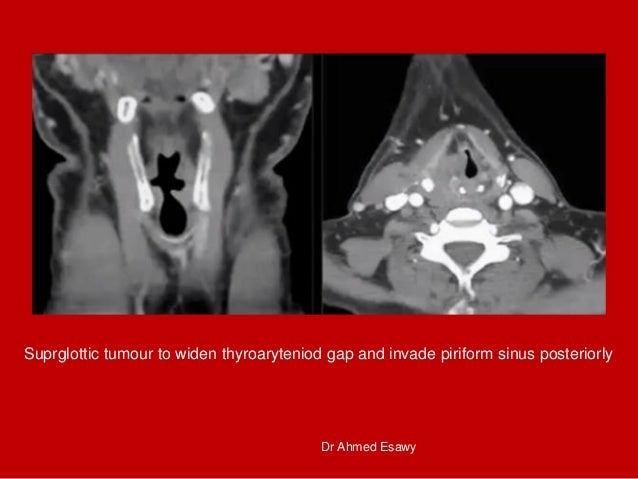

12. 12. Suprglottic tumour to widen thyroaryteniod gap and invade piriform sinus posteriorly Dr Ahmed Esawy